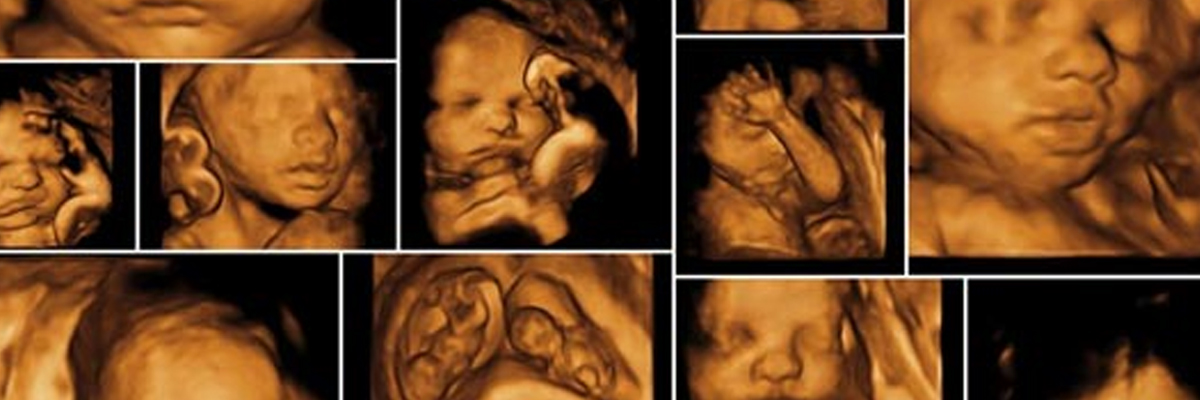

What is 3d and 4d Ultrasound?

3D and 4D ultrasound exams allow you to see your unborn baby in even more depth and detail than a standard 2D ultrasound. In 3D or 4D, you get to see the real image of the baby, i.e., not his/her internal organ but the skin, nose, tongue. You will be able to see what your baby is doing in the uterus, like kicking, yawning, etc. In the 2D screening, the parents can see a faded greyish color of the picture on the screen. This picture appears as the device scans through the baby and shows his/her internal organs.

In 3D Ultrasound, the sonographer records multiple two-dimensional pictures recorded from various angles and then merges them to create a three-dimensional image. For example, you will be able to see your baby in 3D, just like a regular picture on the phone or laptop. You will be able to see his/her face and the whole surface.

• 3D ultrasound: In this method, you will see the image of the baby more clearly. It creates a three-dimensional image of the baby by recording the organs’ internal and external details from different angles. In the monitor, you will be able to see the fetus’s heart, blood vessel or valves, baby’s skin, mouth, or shape.

3D Ultrasound is somewhat the same as 2D Ultrasound, just that they record the waves from multiple angles. The doctors convert multiple images produced from different angles into a single one through sophisticated software. This type of ultrasound algorithm process creates images, which are also known as ‘surface rendering’. . This software produces an accurate portrayal of the fetus and shows it on the monitor. These incredible pictures show a detailed image of the baby’s body and face.